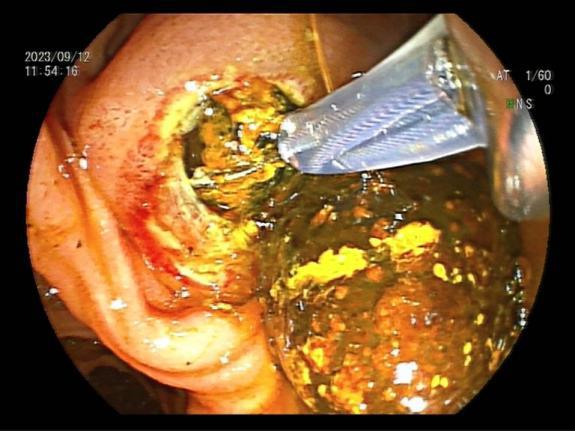

四、内镜下逆行胰胆管造影术(ERCP)

是指将十二指肠镜插至十二指肠降部,找到十二指肠乳头,由活检管道内插入造影导管至乳头开口部,注入造影剂后x线摄片,以显示胰胆管的技术。由于ERCP不用开刀,创伤小,手术时间短,并发症较外科手术少,住院时间也大大缩短,深受患者欢迎。适应于:1. 胆道梗阻引起的黄疸;2. 胰腺或胆道疾患(如结石、肿瘤、硬化性胆管炎等);

胆总管结石造影所见 网篮取出结石

十二指肠乳头癌 十二指肠乳头插管

胆管金属支架置入过程 金属支架置入术后